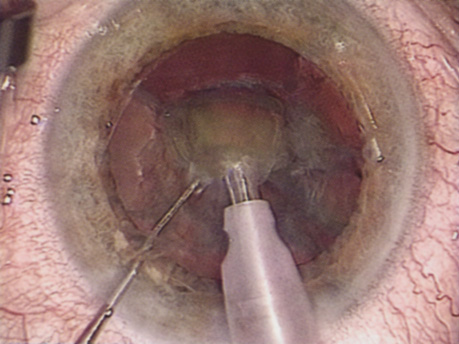

ENDOTHELIAL CELL COUNT.

Although slit-lamp examination can give the ophthalmologist an excellent estimate of endothelial health, sometimes a formal assessment of the corneal endothelial cell density is helpful (Fig. 4). This information is most likely to be helpful in advising patients who may be at greater risk of postoperative corneal decompensation. Specifically, patients with cornea guttata, previous ocular surgery, history of blunt ocular injury,56 exfoliation syndrome,57 iridocorneal-endothelial syndromes,58 or a history of glaucoma59 are known to have reduced endothelial cell counts. Patients with a history of acute angle closure are at particular risk because each episode of elevated intraocular pressure can damage endothelial cells.60

Fig. 4. A noncontact endothelial cell photograph demonstrates a normal cell mosaic and density. The cell count is calculated by identifying those cells within the box and touching two of the four adjacent edges.

There are qualitative and quantitative methods for endothelial cell evaluation. Cell density can be measured directly with an endothelial cell camera. The surgeon also should view the photograph and qualitatively estimate the regularity of the endothelial cell mosaic. Some instruments calculate a coefficient of variability and percent of hexagonal cells.